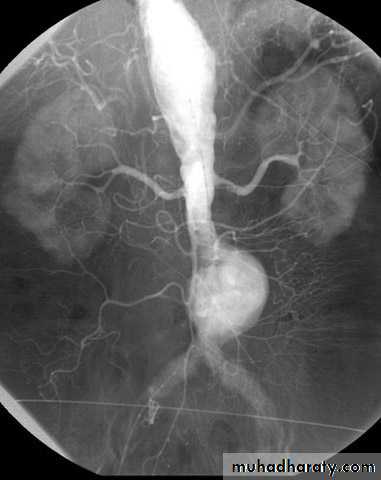

Arteriogram

• (AAAs) is true aneurysms commonly involve the infrarenal aorta. aortic diameter >3 cm = AAA.• An AAA of any size can rupture, but those >5 cm are more likely to rupture.

• The most common location of rupture retroperitoneum